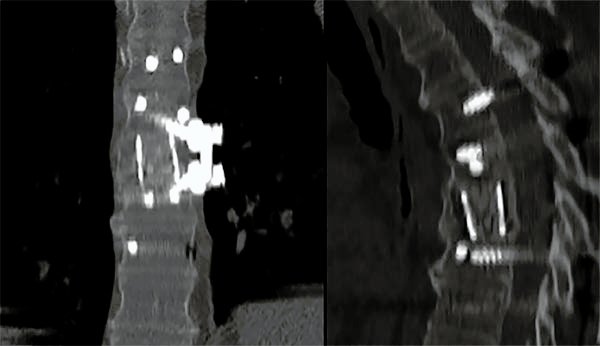

Figura 6:

Caso 8. A la semana de la primer cirugía el paciente se encontraba en condiciones y se realizó la corpectomía por via lateral MIS.

Figura 7:

Caso 8. Control postoperatorio alejado del paciente con un buen callo de fusión, sin pérdida de corrección.